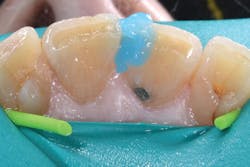

Although the bulk-fill flowable can be placed in larger increments, a small increment was placed first to ensure sufficient curing of the material at the floor of the chamber (figures 3 and 4). The next layer of SureFil SDR flow+ was placed in a 4-mm bulk increment again, followed by 20 seconds of light curing. A final layer of universal composite was placed, occlusion was checked, and after a final polish and postoperative radiograph, the patient was released (figures 5 and 6).